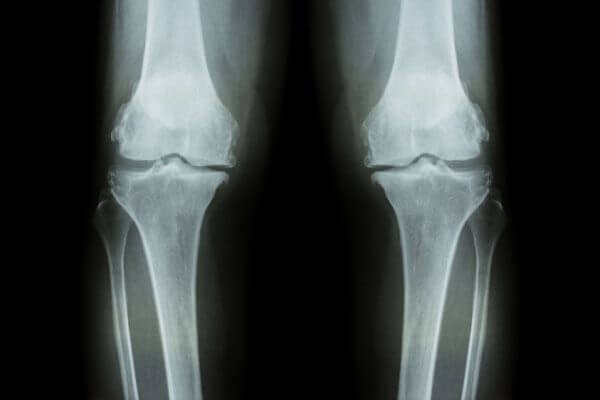

有病人問我,他因為膝關節退化性關節炎,膝關節內半月狀軟骨磨損,關節腔的縫隙空間狹窄,走路會痛,甚至痛到不敢走路,後來甚至不走路也會痛,沒辦法彎曲膝蓋,無法蹲下或坐在地上,坐下也站不起來。這些都是老年人膝關節退化常見的症狀。

二,膝關節退化性關節炎,顧名思義就是膝關節在人體站立和屈膝,以及走跑跳和負荷重物時承受人體體重對抗地心引力,重複的長期動作活動,絕對會帶來磨損、拉扯等傷害和損害(長期過度活動磨損稱作勞損,急性意外事件造成傷害則稱拉傷、扭傷、甚至斷裂、破損)。通常年過五十歲後,尤其是從事勞動工作者,和愛好而積極運動者,因為過度使用和負荷,而膝關節做為人體使用和負荷最大量的關節,難免常見發生“退化性關節炎”的症狀,例如站久、走路、爬坡、屈膝會痛,久之,逐漸站不直,也彎曲不了,又僵硬又腫痛,膝蓋外觀也開始呈現o型或x型的變形(關節腔內側半月狀軟骨磨損厲害者變o形,外側磨損厲害者變x形),當關節軟骨磨損殆盡則長出骨刺在關節腔中,甚至關節腔縫隙消失,上下骨頭融合長在一起,完全喪失關節形狀(變形)和動作功能。退化性膝關節炎一旦到達變形失去功能的程度,只好置換人工膝關節。在初期階段,半月狀軟骨明顯磨損,關節縫隙開始出現狹窄的程度,通常就要積極進行關節腔內注射玻尿酸,開始是一週注射一次,打過3~4次後症狀改善了,可以改為兩週注射一次, 總共需連續注射6~8次(最後一次注射長效型較大分子玻尿酸更好,可以有半年至一年的持續效果)。同時就開給併服“口服型小分子玻尿酸”補充。 療程結束後仍然需繼續長期口服小分子的玻尿酸補充因年老自身不製造只有耗損的情況。年齡未過七十,且看看營養運動體能狀況尚佳者,體內幹細胞數量活力和血漿裡血小板數量和其內部所含生長因子尚稱充足,可以考慮合併採用再生醫學的幹細胞和PRP(濃縮富含血小板血漿)注射治療。通常再生醫學的PRP注射療法是對年青人運動傷害最好的治療方法,對老人嚴重退化的疾病,其實效果並不理想。